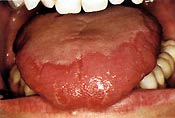

Lichen ruber planus ist ein komplexes Krankheitsbild, das wahrscheinlich durch eine Autoimmunreaktion hervorgerufen wird. Es werden jedoch auch andere Ursachen diskutiert, wie beispielsweise eine Virusinfektion oder eine lokale Immunabwehr. Eine abschließende Zuordnung der Entstehung konnte bisher noch nicht festgelegt werden. An der Wangenschleimhaut, der Wangenumschlagfalte im Seitenzahnbereich, der Zungenunterseite, dem Zungenrücken, dem Mundboden, der Gingiva, dem Gaumen und dem Lippenrot können häufig zierliche, grauweiße, z. T. vernetzte, nicht abwischbare, pustelige Veränderungen vorkommen. Es sind mehr Frauen als Männer befallen. Gehäuft zeigt sich der Lichen ruber planus zwischen dem 4. und 6.Lebensjahrzehnt. Er muss alle drei Monate kontrolliert werden, da er sich sehr variabel darstellt und eine bösartige Entartung möglich ist. Der Lichen ruber soll in etwa 50% der Fälle mit Hauterscheinungen auftreten.